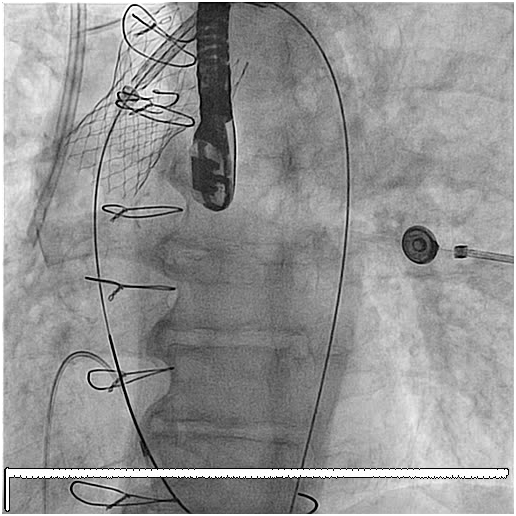

79 y old male patient, known to have diabetes mellitus, end stage renal failure and chronic obstructive pulmonary disease, this patient had aortic valve replacement (AVR) 15years prior, but because of infective endocarditis 7years ago, he underwent a redo AVR (Aortic valve Bioprosthesis) using a 25mm cry preserved aortic homograft implanted as a full root in another hospital. Patient was admitted with severe heart failure and pulmonary edema. His Echocardiogram showed severe AR (Figure 1). Patient was treated aggressively with anti-failure medications. The case discussed in heart team and both options AVR vs TAVI were raised in this high risk patient, with STS score 18. Both the heart team and Family preferred TAVI, According to sizing application this homograft valve will fit with Size 29mm Core Valve, The CT-scan measurements showed an aortic annulus size 21-25mm at different level, Perimeter range from 71-73, 3mm, Aortic valve area 2.9 cm2, and a heavily calcified a tube-like aorta (Figure 2). No clear sinus or junction was seen by CT. A trans-femoral approach for Valve in Valve was used. A 29 mm Medtronic Core valve was deployed and the landmark was the calcium in the root. Unfortunately, it migrated up-ward most probably due to the rigidity of the homograft tube and no real narrowing or calcified leaflet to anchored the valve (Figure 3). Therefore we used another 29 core valve and deployed it through the first one which was well seated in ascending aorta as support. This method of support was very successful for final deployment (Figure 4). It was similar to the melody valve deployment in treating pulmonary regurgitation. There was no aortic regurgitation by Echocardiogram (Figure 5). Patient was very stable and discharged home after 48hours.

Figure 1 Echocardiogram image showed a color Doppler with a severe aortic regurgitation.